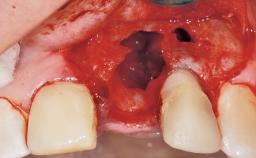

A 30-year-old female patient was referred to the office for the treatment of tooth 11. Her chief concern at the initial visit was to inquire, “Why is my tooth pink?” Upon clinical examination, it was determined that tooth 11 had a previous history of trauma and that the clinical crown had become noticeably pink in color as a result of internal resorption. This diagnosis was confirmed radiographically, indicating a large radiolucency involving the central and distal portions of the clinical crown. It was determined that restoration of this tooth was not possible, and that extraction was indicated. The presence of a mid-line diastema, which the patient wanted to reproduce, directed the treatment plan for tooth replacement utilizing a dental implant.

Bone Augmentation Horizontal|Simultaneous

Augmentation Materials Autogenous chips|Membrane

Socket Integrity Sufficient, with intact bone walls

Bone Volume Sufficient, with intact walls